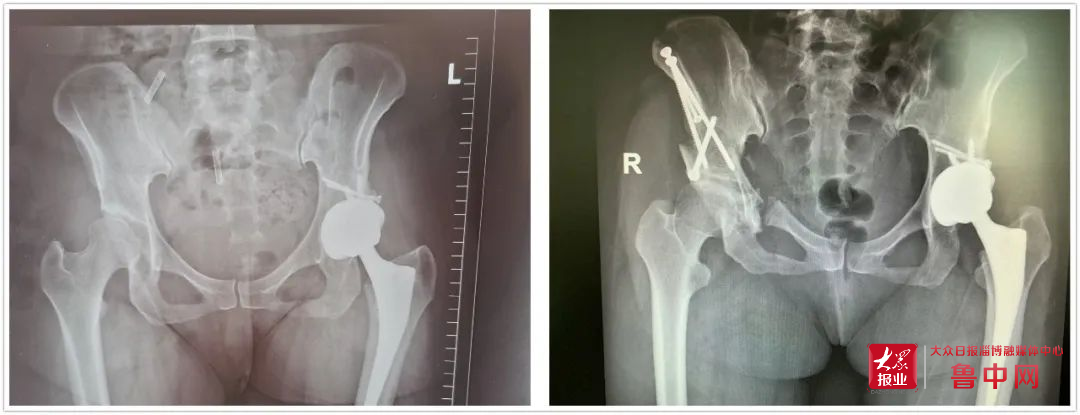

骨外科主任方俊英接診胡女士后,對其進行詳細的問診和查體,并結(jié)合拍片檢查發(fā)現(xiàn)了右髖已出現(xiàn)輕度的關(guān)節(jié)炎。出于有過同樣手術(shù)經(jīng)歷的胡女士,深知全髖關(guān)節(jié)置換術(shù)的“后遺癥”。于是胡女士向方主任求助是否有更佳治療方案。方主任得知其顧慮后,立即組織骨外科專家對胡女士的病情進行討論,結(jié)合胡女士的影像資料及癥狀,考慮行髖臼周圍截骨術(shù)是最佳治療方案,既可以緩解癥狀,又可以延緩骨關(guān)節(jié)炎的發(fā)展,延期甚至無需接受全髖關(guān)節(jié)置換術(shù)。但因其髖臼周圍解剖復雜、手術(shù)難度大,目前能做此手術(shù)的專家甚少,北大醫(yī)療淄博醫(yī)院合作的山東第一醫(yī)科大學第一附屬醫(yī)院,骨關(guān)節(jié)外科李樹鋒主任正是其中一位。于是通過遠程會診系統(tǒng)在線邀請李樹鋒主任會診,結(jié)合患者病情,為其制定了詳細的手術(shù)方案。

經(jīng)過完善的術(shù)前準備,手術(shù)如期進行。術(shù)中經(jīng)過多次精確測量和截骨,在透視下逐一完成髂骨、恥骨支的截骨。在最難實施的坐骨支截骨階段,李樹鋒主任、方俊英主任以及骨外科專家團隊克服了坐骨周圍肌肉和深部組織的影響,完成了坐骨—髂骨截骨銜接,并一舉旋轉(zhuǎn)固定成功。手術(shù)經(jīng)歷三個多小時順利完成。在醫(yī)護人員的精心治療下,術(shù)后1周恢復良好,康復出院。